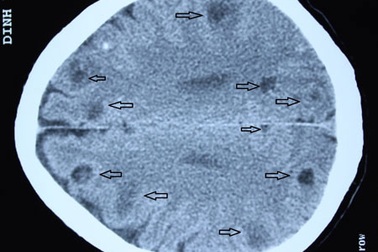

Phát hiện gần 50 ổ sán trong não bệnh nhânMột bệnh nhân được đưa đến BV Bệnh Nhiệt đới Trung ương trong tình trạng lơ mơ, xuất hiện các cơn co giật. Kết quả chụp CT sọ não các bác sĩ phát hiện trên dưới 50 ổ sán trong não bệnh nhân.